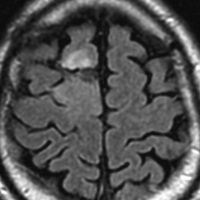

グレード2:良性の乏突起膠腫の例

認知症で発症した60代男性の乏突起膠腫です。巨大で周囲の脳を圧迫する腫瘍でしたから,手術で部分摘出した後に放射線も化学療法も何もしないで経過観察しましたが,患者さんは社会復帰して仕事に戻れました。その後,無治療で13年が経過した時のMRIです。この13年間にほとんど大きくなっていません。このように高分化型とされる乏突起膠腫には,何もしないで様子を見ても長期間にわたって増大しない良性のものもあります。